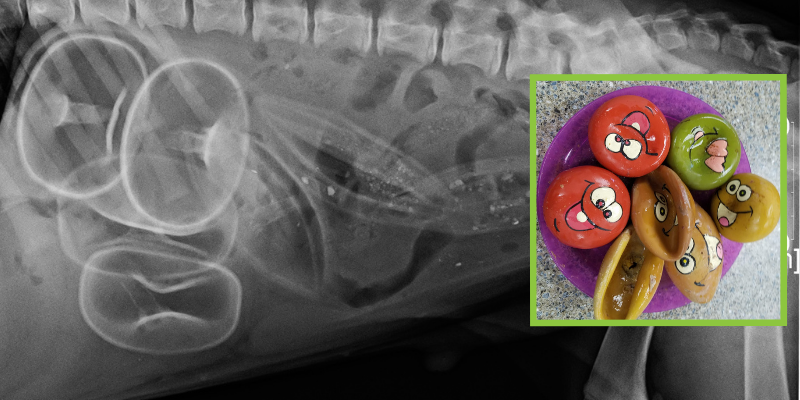

X-ray of dog who ate seven squeaker toys & had them surgically removed.

Dogs and cats are notoriously curious creatures, which can sometimes lead them into trouble. Many times, this curiosity leads them to eat items not intended for ingestion! Socks, underwear, wrappers, rubber bands, yarn, corn cobs, toys – you name it, there’s probably a pet who has eaten it! In the animal ER, we call these items “foreign bodies,” and while sometimes they will pass through a pet’s GI tract with no problem, they can also be a true emergency that requires immediate surgery. So whether your pet is new to this rebellious lifestyle or is a repeat offender, here’s what pet parents need to know about foreign body ingestions!